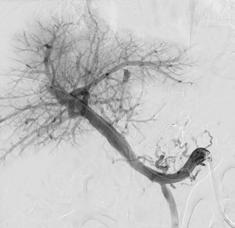

Chief of Neuroradiology Vinil Shah, MD, treated Pascual with kyphoplasty – a minimally invasive surgical procedure that stabilized vertebral compression fractures caused by the cancer in his spine – to reduce pain and restore the affected vertebrae for better mobility.